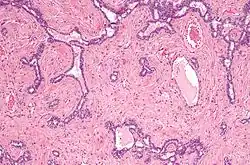

Micrograph of the rete testis involved by seminoma. H&E stain. -